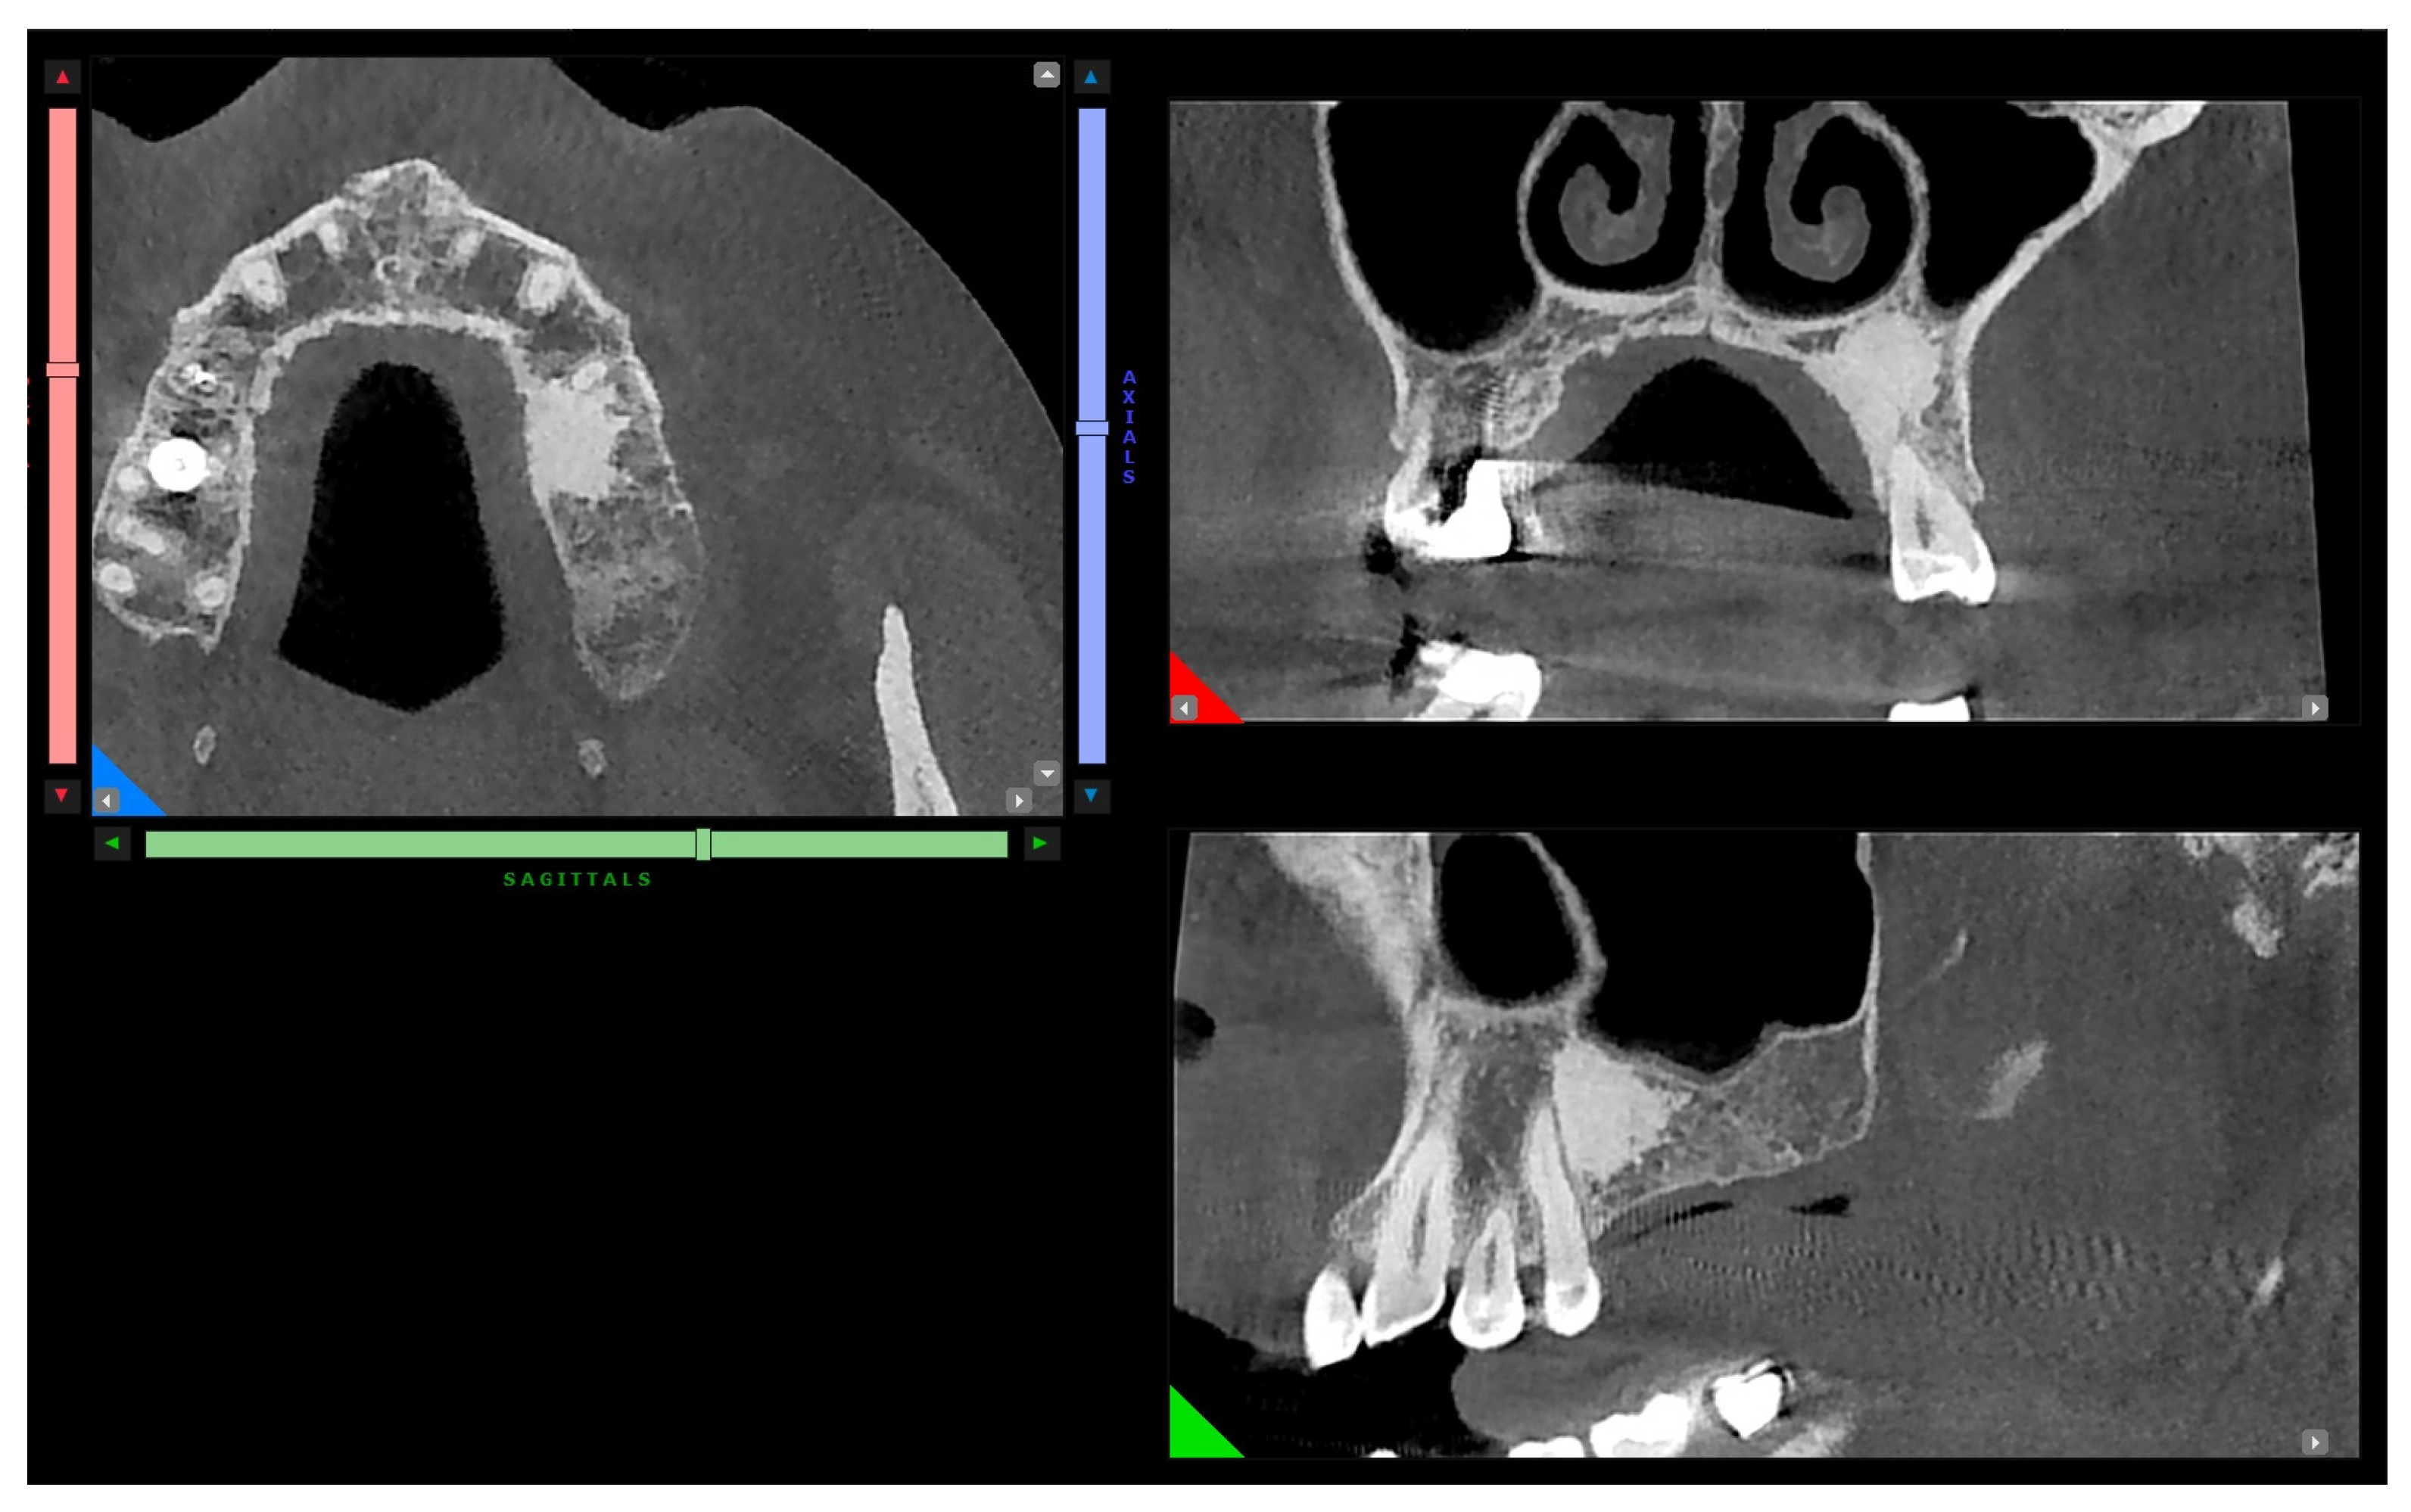

The patient was sent to the oral surgery specialist, who recommended the second-level X-ray examination (CBCT) due to the diagnostic doubt in the panoramic X-ray, thus involving a third specialist, the radiologist. The 3D exam was performed by an oral and maxillofacial center with a cone beam CT scanner with low-dose ionizing radiation, isotropic volume, and a 12 cm field. Axial, panoramic, and cross-section images (dental scan modality) were obtained by multiplanar reconstruction. Image dimensions were real to give the possibility of thickness and distance measurement. A three-dimensional X-ray showed a bone island of juxtacortical hyperdensity and defined edges in the premolar region of the left maxilla (Figure 3).

Figure 3.

Axial, sagittal, and paracoronal view of the hyperdense finding in CBCT examination.